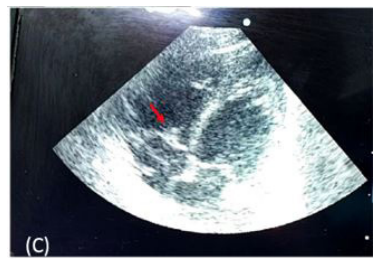

| Figure 3:Vegetation on anterior tricuspid leaflet (arrow) on echocardiography |

There was also gangrene of left foot big toe tip (Figure 1) for which subcutaneous low molecular weight heparin was started. Blood investigations showed leukocytosis (total leukocyte count – 15.3 x 106/L, polymorph 69%) and an elevated CRP (101mg/dl). X ray showed right ICD tube in situ with no residual pneumothorax. There was bilateral haziness suggestive of pneumonia and also a left midzone pneumatocele (Figure 2). This was later ultrasonographically detected to be left upper lobe collapse consolidation with air bronchogram. Screening bedside echocardiography was done and it revealed swinging vegetations on tricuspid valve leaflet. A structurally normal heart with patent foramen ovale and vegetations over anterior tricuspid valve of size 0.32cm was subsequently confirmed by pediatric cardiologist (Figure 3). Doppler flow imaging for of lower limb vessels was normal.